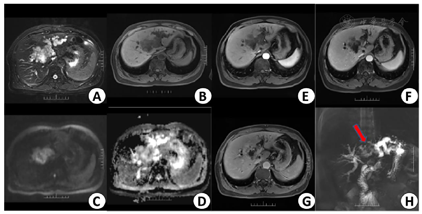

3月12日上腹部增强CT提示肝门部胆管癌可能(图1)。3月13日B超提示肝门部至胆总管上段占位,考虑肿瘤伴胆管受侵可能。3月16日上腹部增强MR提示肝门部胆管癌伴胆道梗阻可能(图2)。3月12日实验室检查示,AFP为8.1 ng/ml,CEA为1.61 ng/ml,CA50为68.76 IU/ml,CA19-9为80.89 IU/ml,ALT为126 IU/L,AST为76 IU/L,TBIL为77.7 umol/L,DBIL为62.5 umol/L。

考虑到患者较年轻且患者及家属治疗欲望强烈,希望予以手术根治。为防止患者术后残肝脏体积不足发生肝衰竭,目前国内外多数学者主张采用术前行保留侧肝脏的PTCD和(或)切除侧肝门静脉栓塞(portal vein embolization,PVE)以使保留侧肝脏获得代偿性增生从而降低广泛肝切除的危险性[3]。4月3日患者于我科行PVE,术中予以生物胶+碘油+弹簧圈组合充分封堵门静脉左支主干。4月16日复查CT示左肝大片状碘油沉积,右肝代偿性增生(图3)。4月30日拟行胆管癌根治术,术中示肿瘤位于肝门汇合部,包裹肝十二指肠,大小约8 cm×4 cm,质硬,肝门部可见肿大淋巴结,无法行肝门部胆管癌根治术,遂行"剖腹探查术+开腹肝活检术+胆囊切除术"。术后免疫组化结果(图4)示肝脏: CA199 (小胆管+),CK19(小胆管+) ;CK7(胆管上皮+),HepPar-1(+),GPC3(-),AFP(-);CK20(-),K1-67(+,2%);淋巴结Kappa(+),Lambda(+),CK(-)。